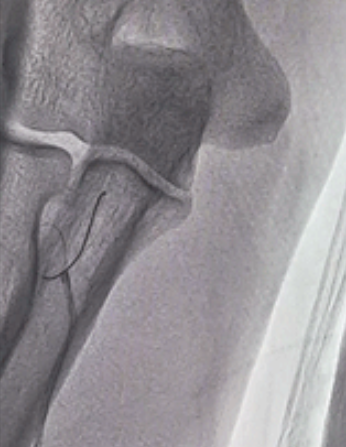

图3 BAT技术球囊引导导管通过弯曲

图4 导管通过成功弯曲